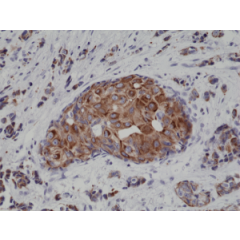

anti-Cytokeratin-19 (human), Rabbit Monoclonal (RM364)

anti-Cytokeratin-19 (human), Rabbit Monoclonal (RM364)

REV-31-1249-00 REV-31-1249-00-R100 100 µl CHF 468.00